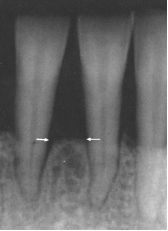

Naast deze 'klinische' gegevens is het belangrijk om ook röntgenfoto's van de tanden en kiezen te hebben. Op deze foto's is het verloop van het botniveau tussen de tanden en kiezen te beoordelen, maar kunnen ook andere problemen, welke van belang zijn voor de behandeling, opgespoord worden.

Boven zijn twee röntgenfoto's te zien, op de linker is een normaal botniveau zichtbaar, terwijl op de rechter foto, het botniveau sterk verlaagd is door parodontale afbraak.